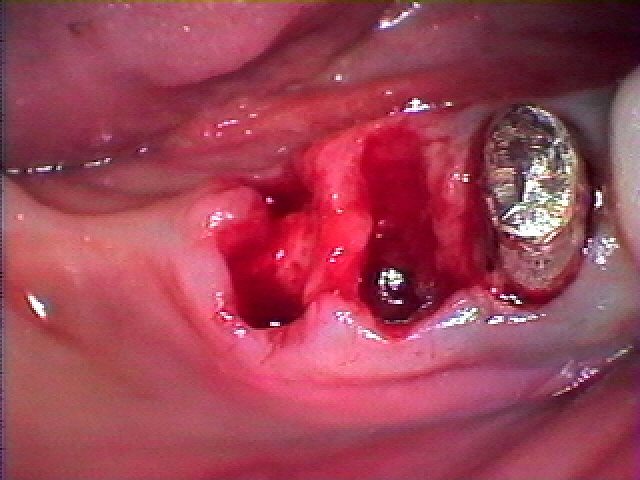

お話をして抜歯をさせていただきました

入れ歯はしたくないとのこと、インプラントは予算は1本まで

とのことで6番だけインプラントを埋入していきます

インプラント埋入時になります